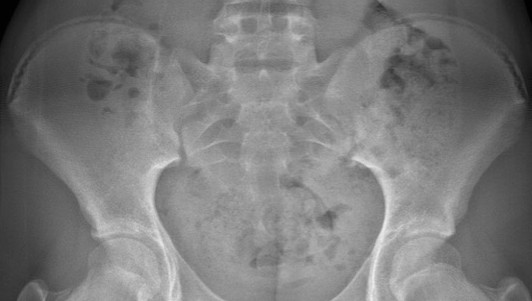

*Risser sign : stage3 에서 stage4로 넘어가는중

사춘기 후반에 중요한 Risser sign 또한 stage3 에서 stage4로 넘어가는중으로 확인되었습니다. 그렇다는 얘기는 추후에 자랄수 있는 기간이 많이 남아있지 않다는 의미였습니다.